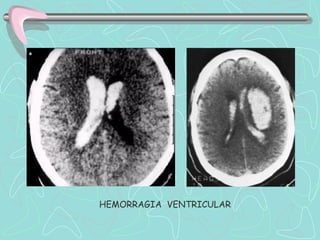

01.02. HEMORRAGIA INTRAVENTRICULAR

B.     HEMORRAGIA VENTRICULAR

 Colección de sangre en el interior de los

ventrículos cerebrales.

Primaria. Sangrado se localiza de forma exclusiva

en el sistema ventricular.

Secundaria . Originada en el espacio subaracnoideo

o en el parénquima y que se ha extendido al

sistema ventricular.

HEMORRAGIA VENTRICULAR